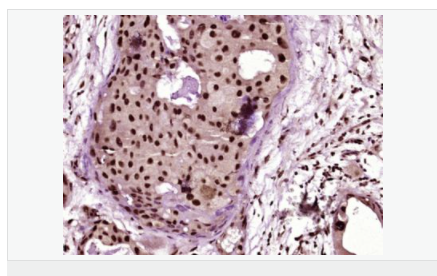

| 產(chǎn)品應(yīng)用 | ELISA=1:5000-10000 IHC-F=1:100-500 ICC=1:100-500 IF=1:100-500 (石蠟切片需做抗原修復(fù)) not yet tested in other applications. optimal dilutions/concentrations should be determined by the end user. |

| 免 疫 原 | KLH conjugated synthesised phosphopeptide derived from human GRK2 around the phosphorylation site of Ser670:PR(p-S)PV |